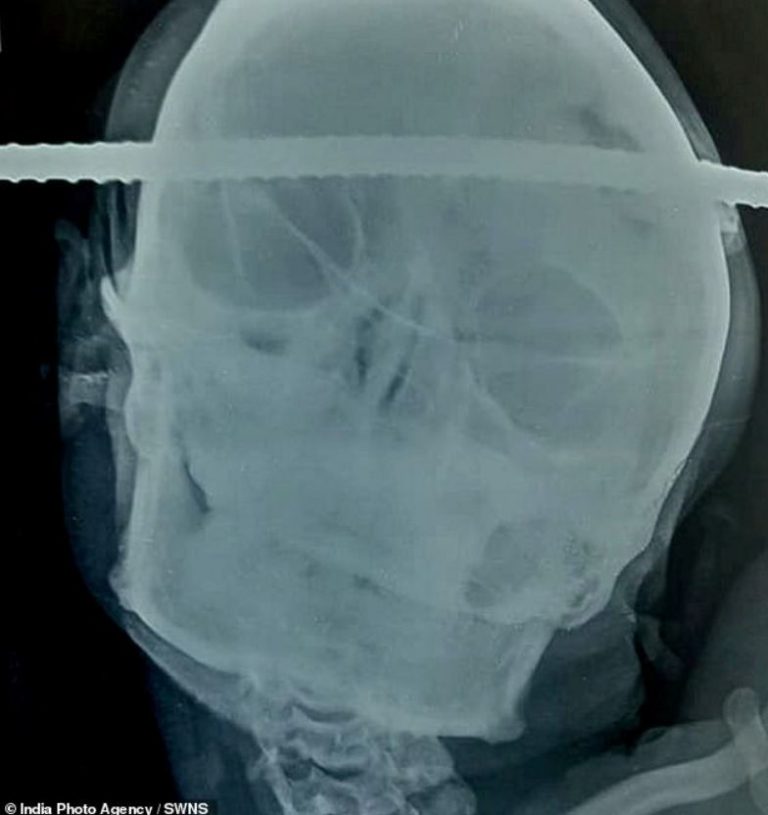

A 21-year-old Indian man has undergone a successful operation to remove an iron rod that pierced through his skull.

On Wednesday, one Sanjay Bahe was recorded calmly talking to medics with the iron rod sticking out of both sides of his head before it was safely removed.

He was building a well at his family farm at Balaghat, Madhya Pradesh, when he fell onto the metal rods, with one piercing the right side of his skull, passing through his brain and coming out of left side of his head.

Neurosurgeon Dr. Pramod Giri said the rod entered the right temporal region of the brain and passed through the left frontal region across the midline.